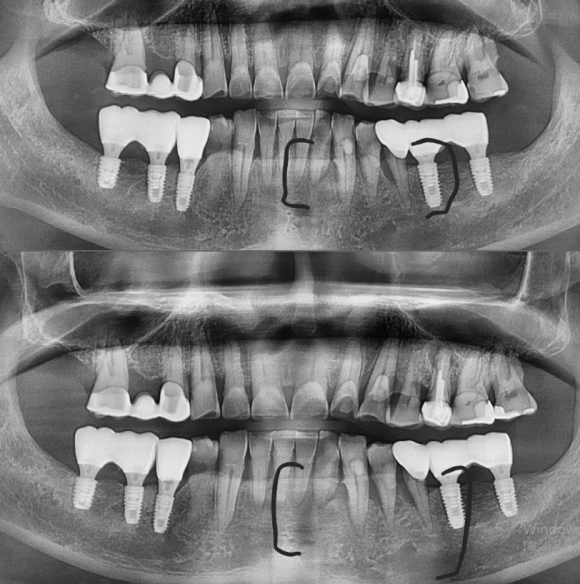

2019년 첫 방문 당시 (위사진) 잇몸질환이 급격하게 진행중이므로 반드시 4~5개월에 한번씩 스케일링을 받으러 오라고 했지만... 전화와 문자를 보내도 오시지 않다가.. 2023년 1월, 잇몸이 다 무너진 상태(아래사진)로 내원하신 60대 남성 환자분 입니다. 다른 부위를 보셔도 알겠지만.. 아프지...

2019년 첫 방문 당시 (위사진) 잇몸질환이 급격하게 진행중이므로

반드시 4~5개월에 한번씩 스케일링을 받으러 오라고 했지만...

전화와 문자를 보내도 오시지 않다가..

2023년 1월, 잇몸이 다 무너진 상태(아래사진)로 내원하신 60대 남성 환자분 입니다.

다른 부위를 보셔도 알겠지만..

아프지 않으면 치과를 가지 않는 습관을 가지고 계신 것을 알 수 있습니다.

왜냐,

스케일링과 정기검진으로 관리하신 분들과, 아프면 (=증상이 생기고 늦으면..) 오는 분들의

치료 히스토리와 (사진상 보임) 잇몸건강 자체가 다르기 때문이지요.

치과치료는 반드시 사진에 남게 되니까요.